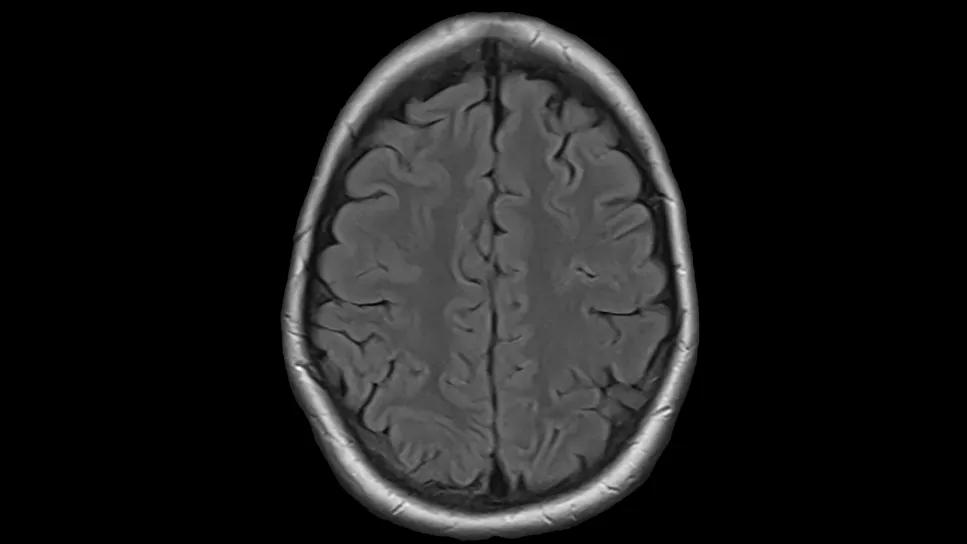

A 21-year-old patient with aggressive lymphoma sought care at Cleveland Clinic Cancer Institute after rapid acceleration of her disease. Caring for a young patient with lymphoma and swift progression to central nervous system (CNS) disease…